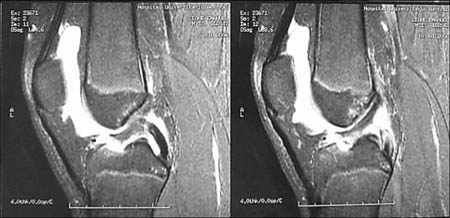

Resonancia Magnética Nuclear. Se utilizo un resonador General Electric 1.5 Tesla. (Fig. 2)

Figura 2: RMN. Desinserción del tendón rotuliano en polo inferior patelar, encondroma fémur distal.

Se realizó el diagnóstico clínico de la lesión (impotencia funcional, dolor y brecha infrapatelar) y luego los métodos de imágenes complementarios confirmaron las lesiones. Mediante RNM se pudo esta- blecer el nivel de la lesión, con 9 desinserciones a nivel del polo distal de la rótula y 1 rotura mediotendinosa en el tendón patelar.